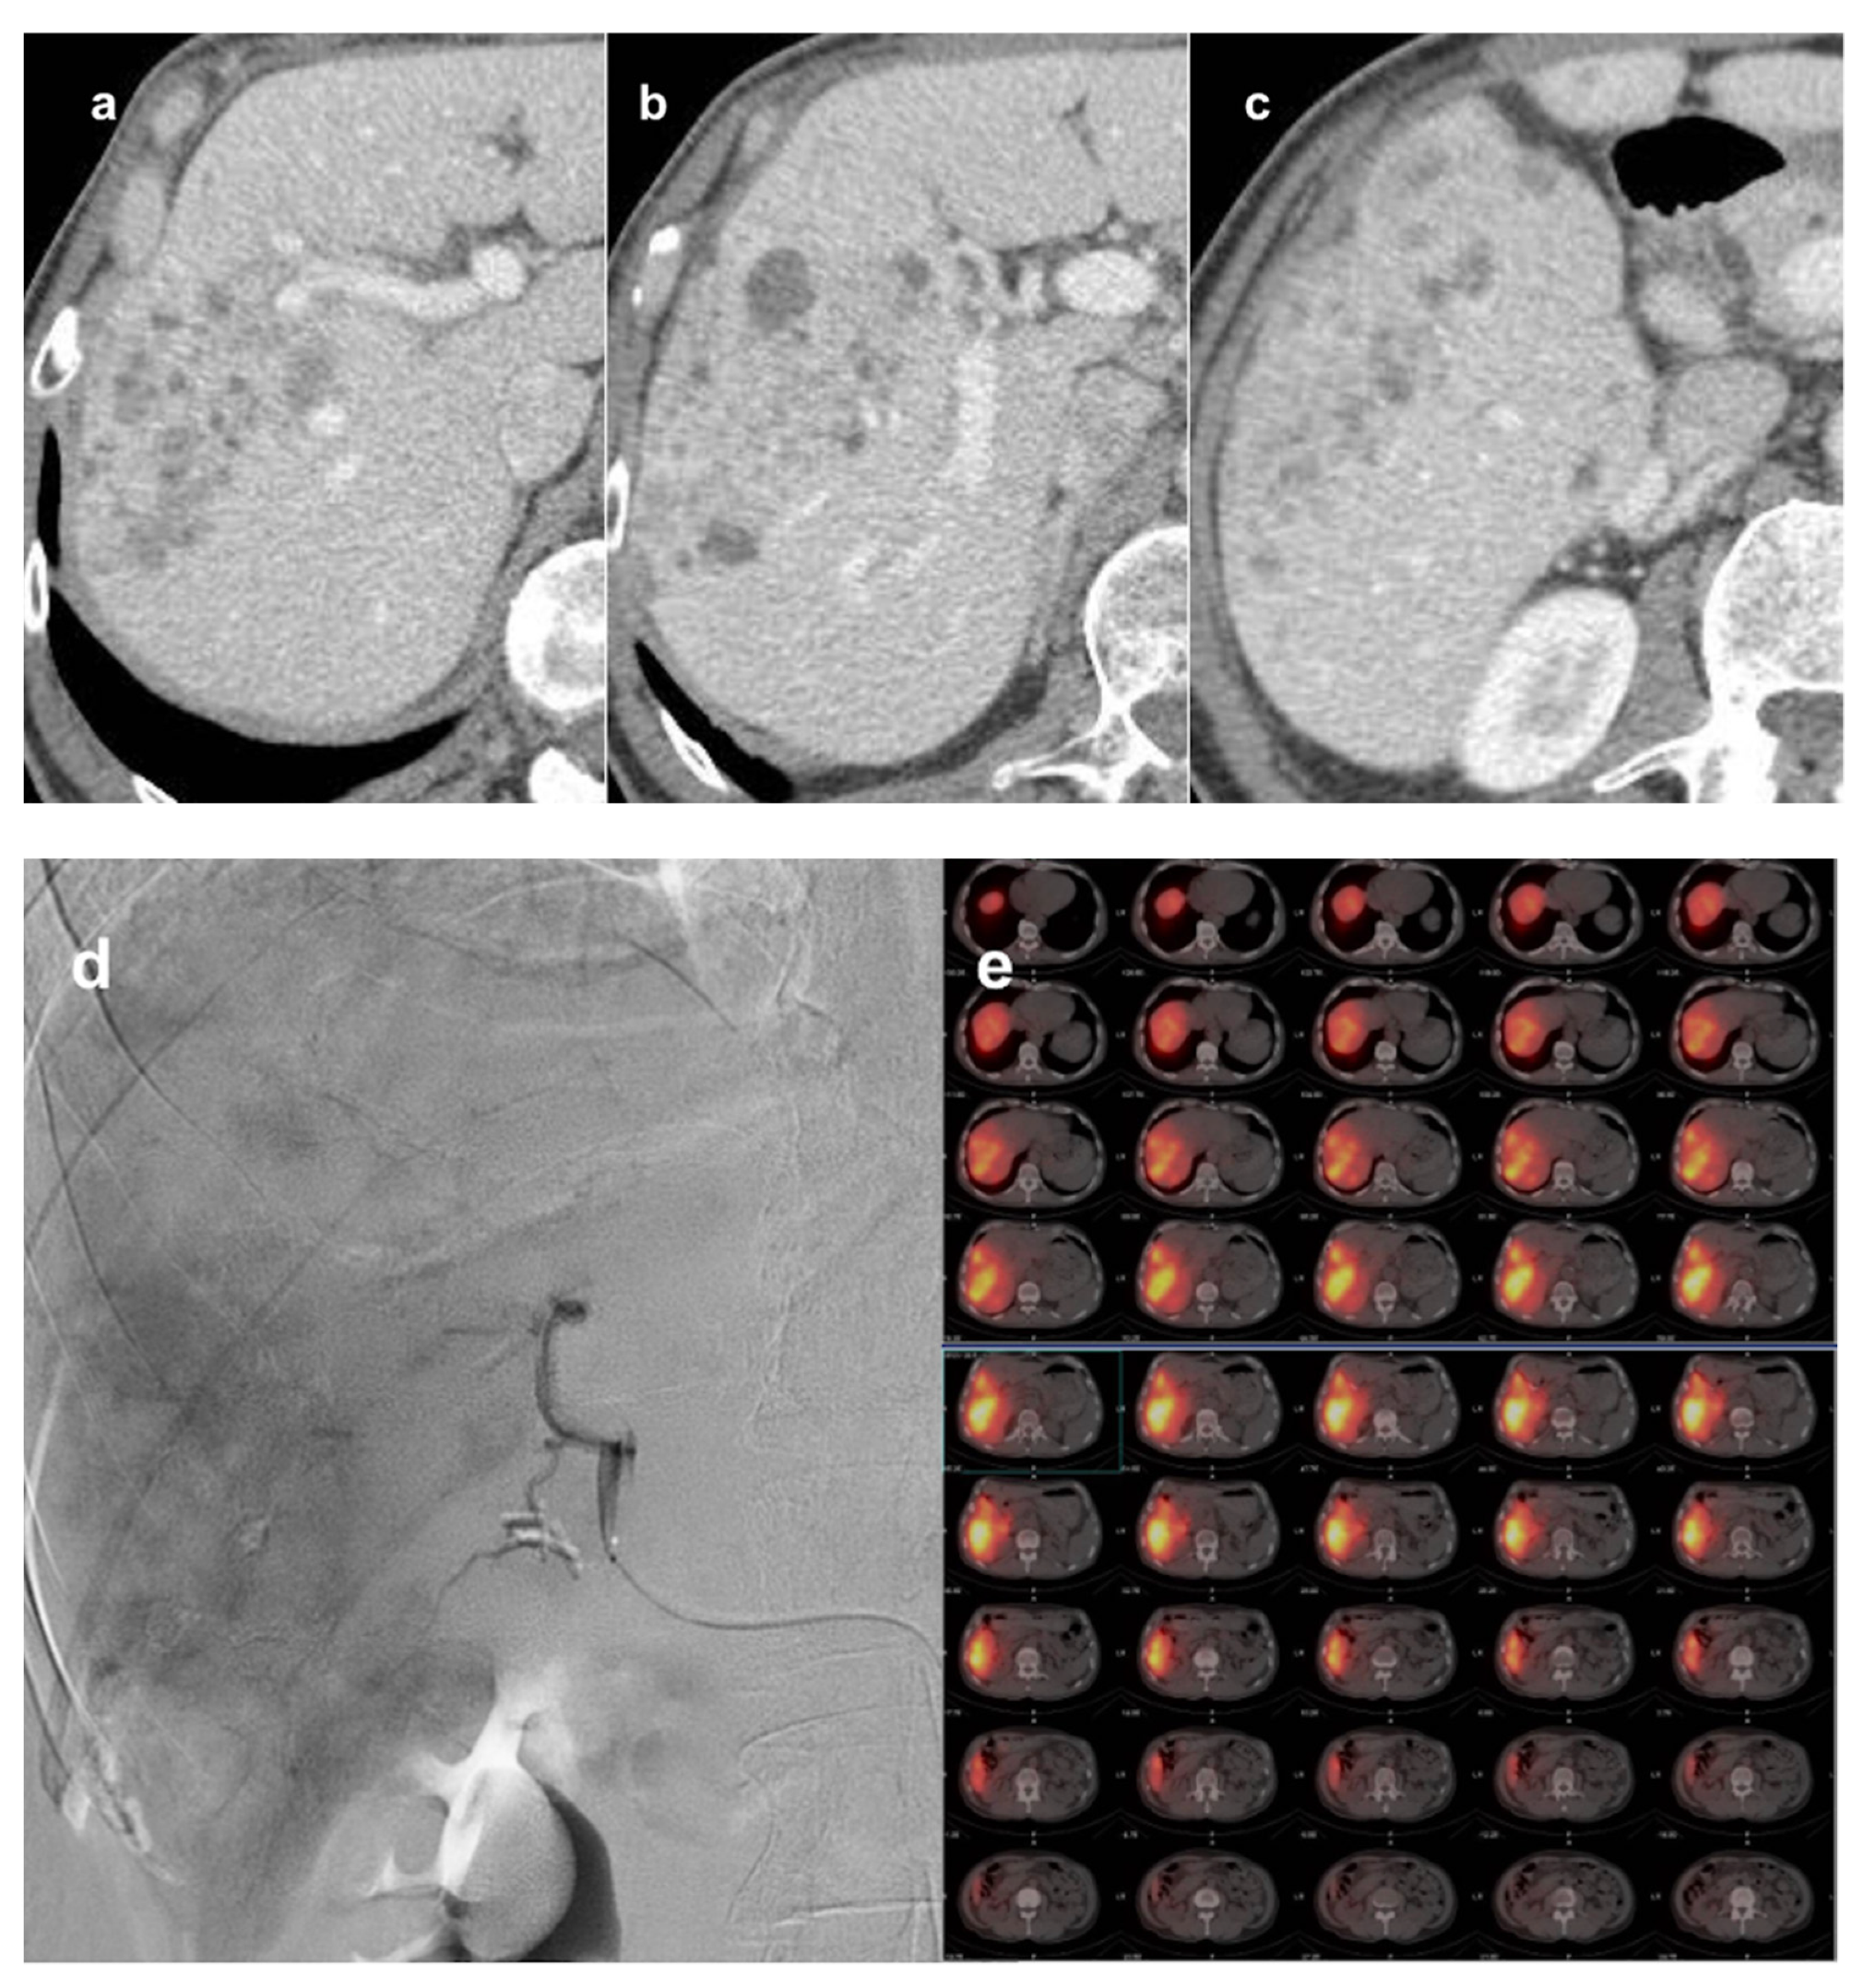

- Levi Sandri, G.B.; Ettorre, G.M.; Colasanti, M.; De Werra, E.; Mascianà, G.; Ferraro, D.; Tortorelli, G.; Sciuto, R.; Lucatelli, P.; Pizzi, G.; et al. Hepatocellular Carcinoma with Macrovascular Invasion Treated with Yttrium-90 Radioembolization Prior to Transplantation. Hepatobiliary Surg. Nutr. 2017, 6, 44–48. [Google Scholar] [CrossRef] [PubMed] [Green Version]